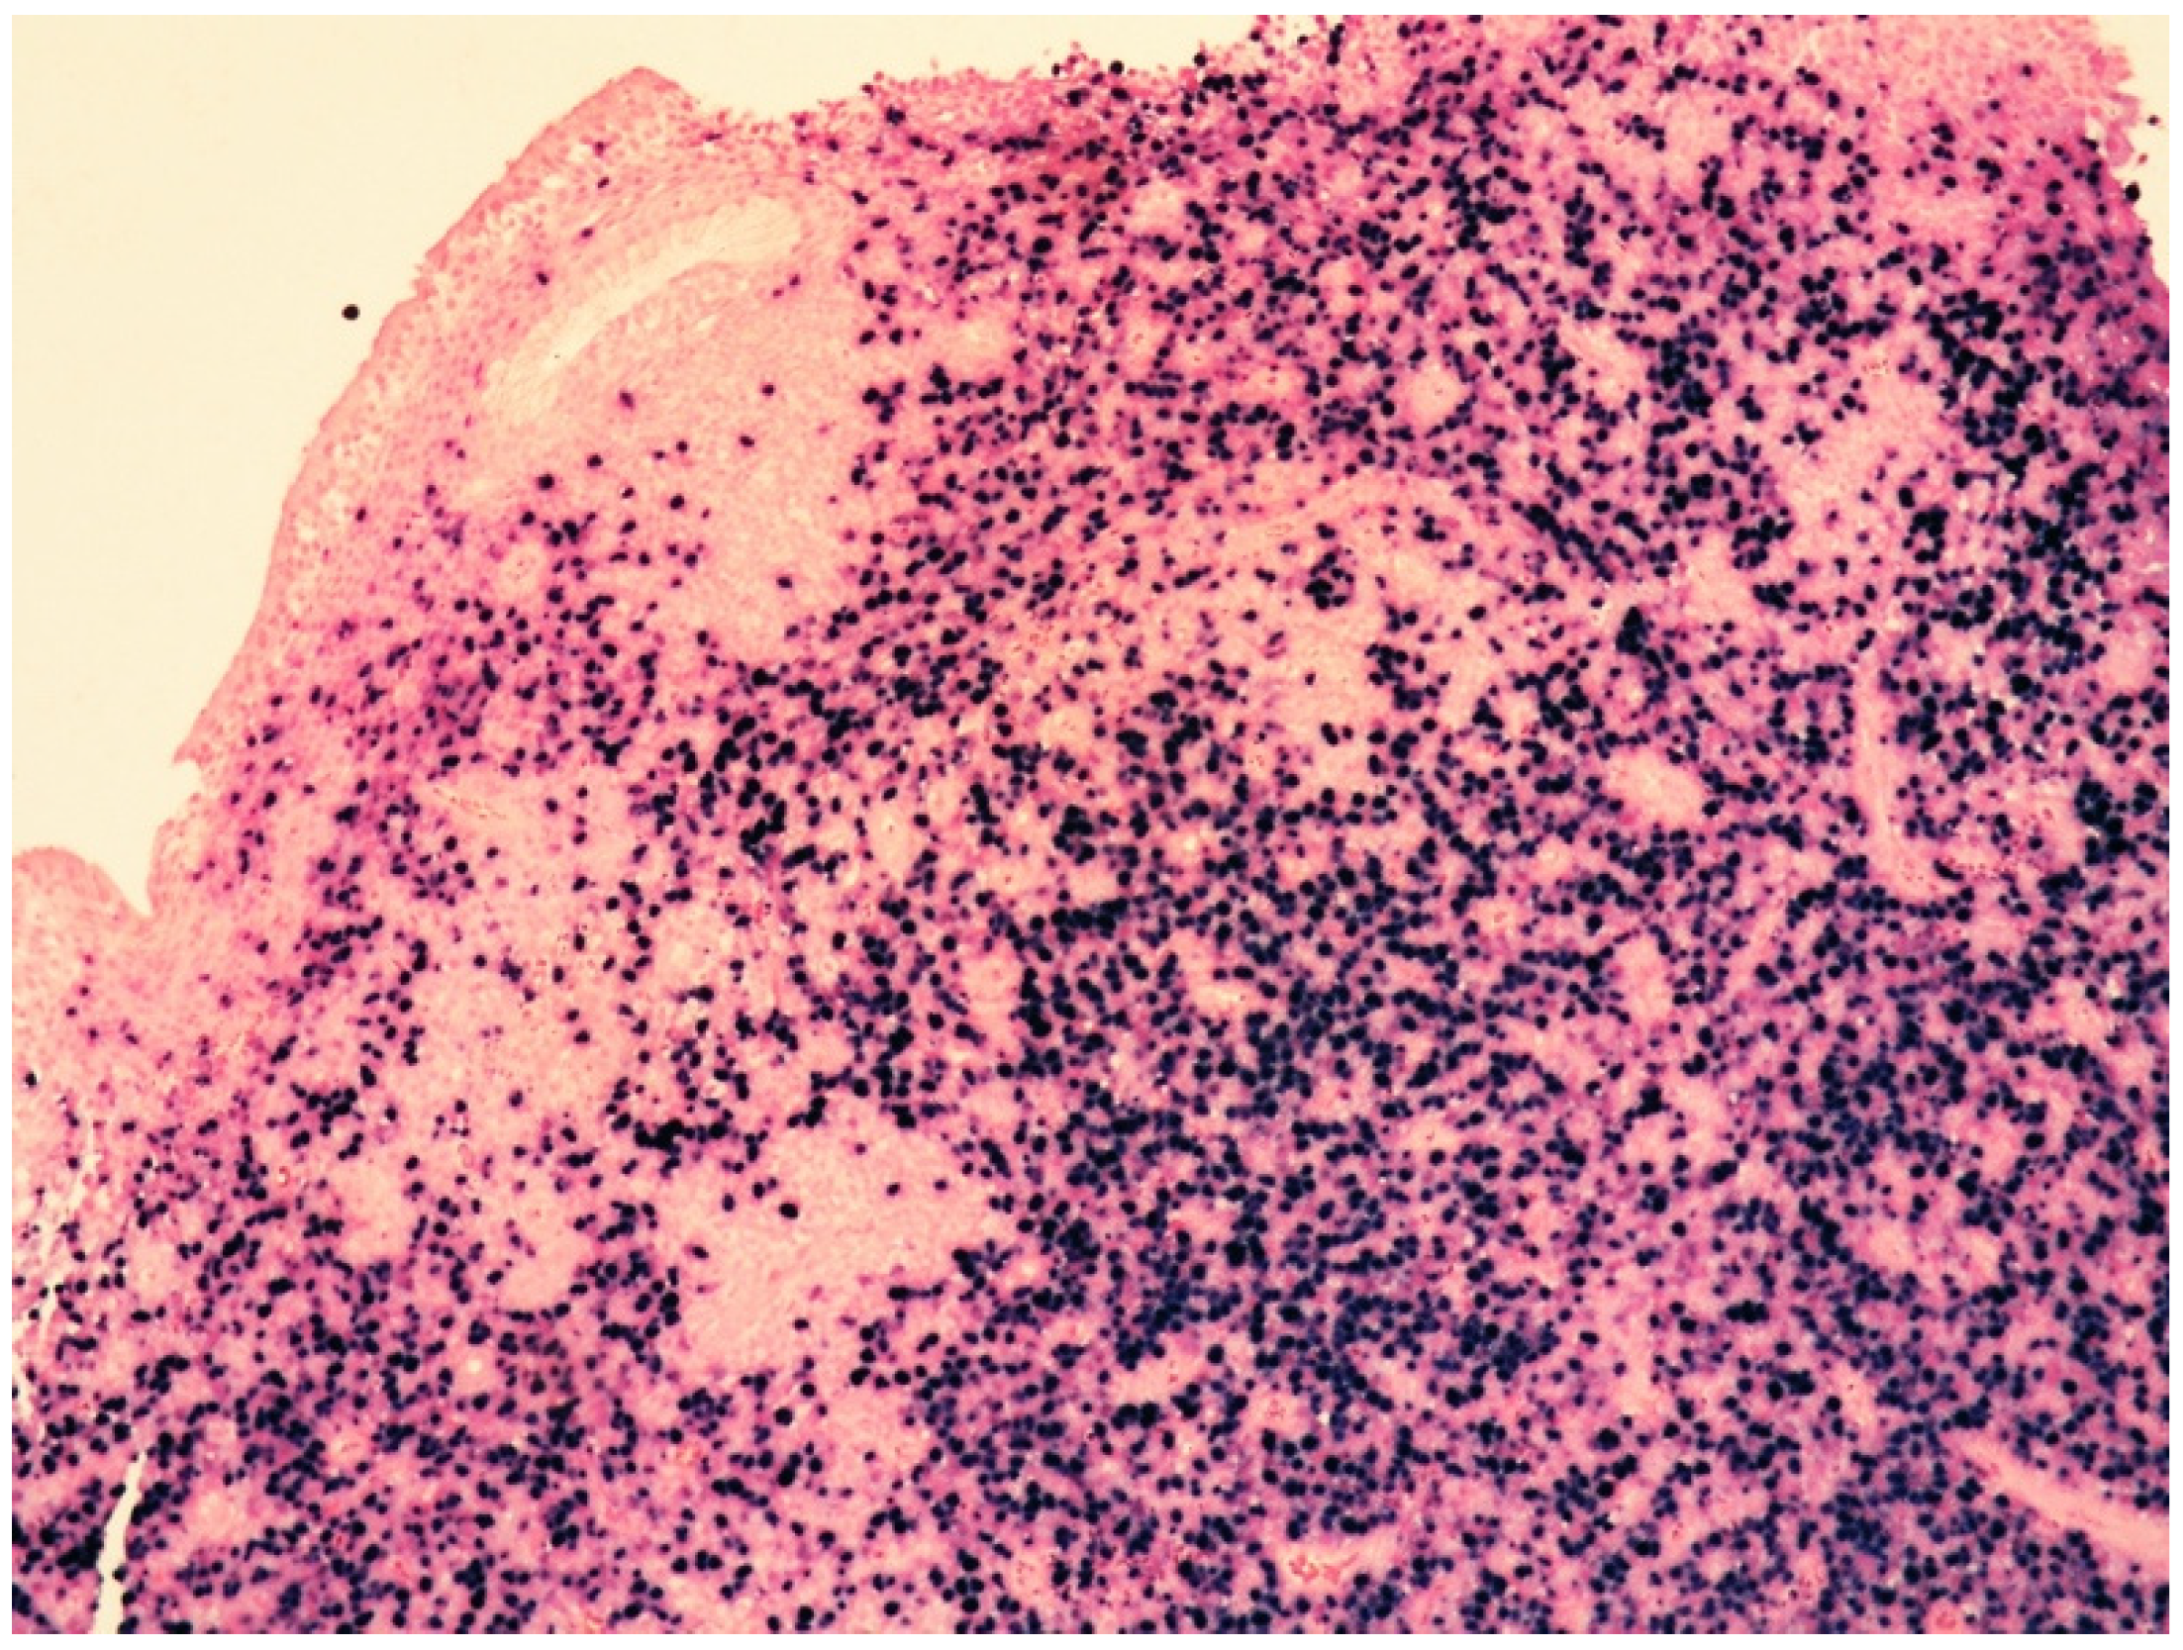

Histologically, the tumor cells are usually discohesive, pleomorphic, and large-sized, with scant cytoplasm and irregular, enlarged nuclei showing hyperchromatic nucleoli; the cells grow inside the lumina of small- to medium-sized vessels without forming a mass (Figure 1 and Figure 2).

The majority of NK/T-cell IVL express either T-cell (Figure 3) or NK-cell markers (CD56) and cytotoxic molecules such as granzyme B and perforin (Figure 4).

Figure 3. Medium-power view showing bone marrow with CD3-positive atypical cells within sinusoidal spaces (CD3 immunostaining, 100× magnification, previously unpublished, original image from S.A.).